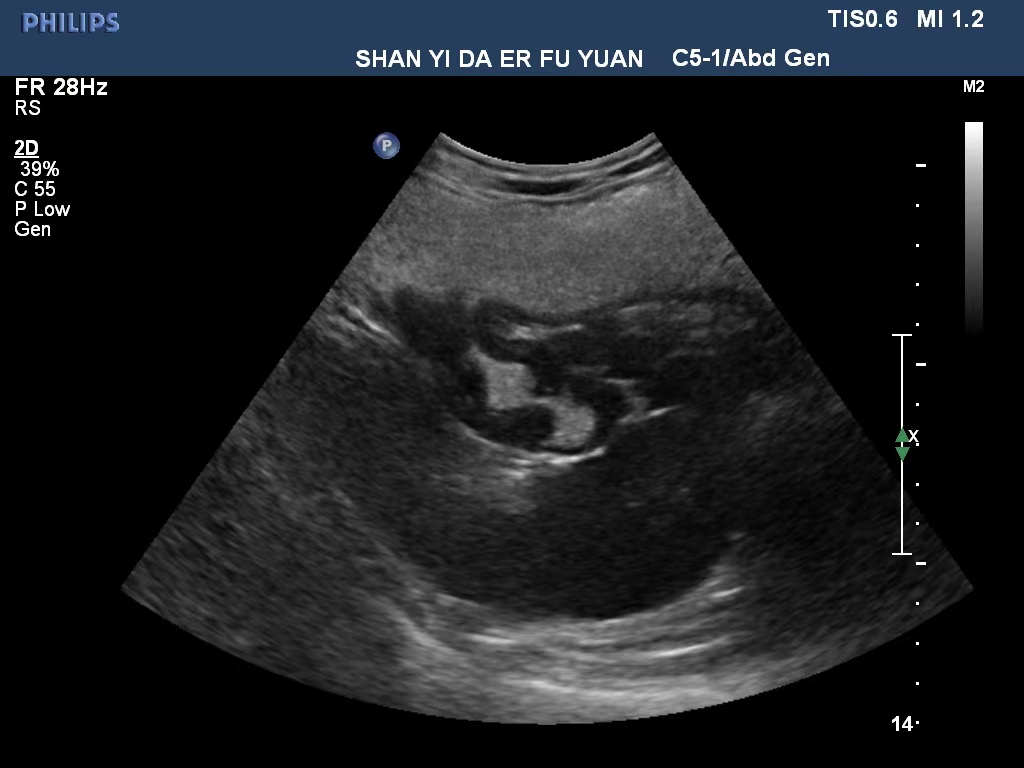

胃潰瘍